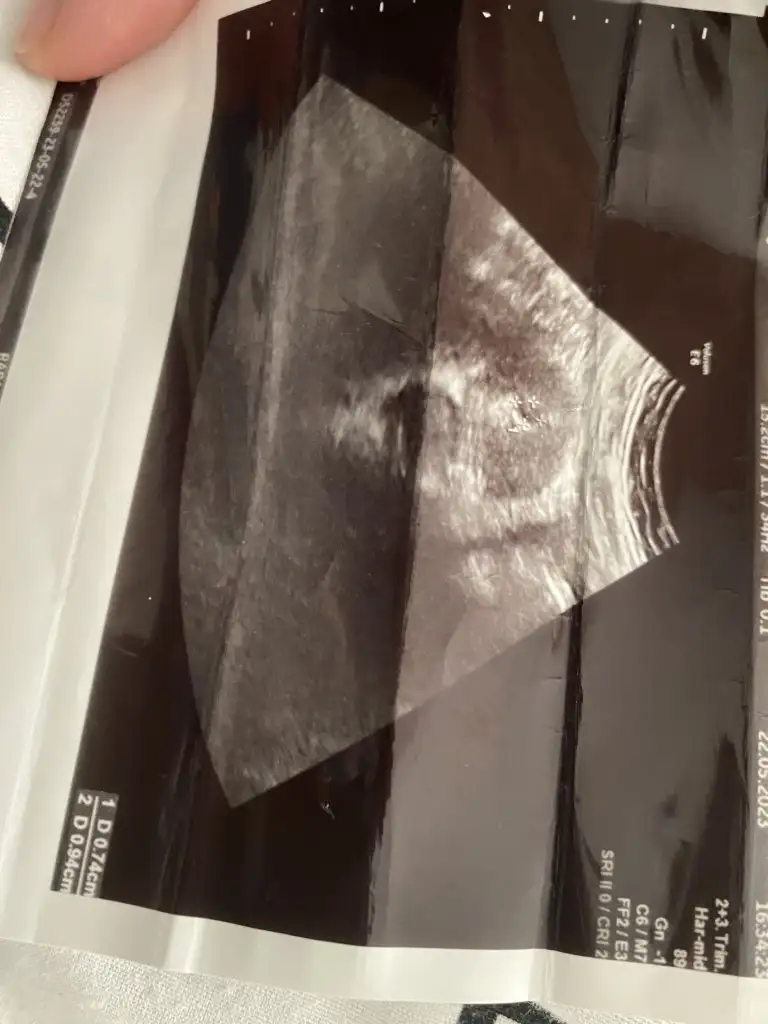

Teşekkür ederim. Kese 13.2 mm. Bebek de 3 mm olmuşTebrik ederimkeseniz kaç mm olmuş acaba

Vajinal baktı mıBen bugün dayanamadım yine gittim kese.14 mm yine gözükmüyor ama doktor emin olamadi 3 kez baktı yine de sne bilirsin haftaya gel kürtaj olursun dedi![]()

Keseniz 6+3de mi 8.6 mmydi?Benim de sat 22 Mart. Cuma günü gitmiştim doktora. Sata göre 6+2 ydim. Siz de 6+3 olmanız gerekiyor doktora gittiğiniz gün. Benim kesem 8.6 mm idi ve doktora kese için çok iyi dedi. Biz de yolk ve bebek göremedik ama doktor olumsuz konuşmadı ve haftaya gel dedi. Sizin neden kese için haftayla uyumlu değil demiş doktor acaba? Ultrason resmi var mı acaba?

Merhaba bende bugün doktora gittim görüntü yok ama rapora bunları yazmış ys pozitif ne demek acaba bilginiz var mı, kist var bu arada onu belirtmiş raporda onu gördüm ama üstte yazandan birşey anlamadım, sata göre 5+4 günlük kese var bebek yok daha öncede boş gebelik yaşadım konuşmak için erken dedi ama korkuyor insan ister istemezbak o işaretledigim alandakş yuvarlak var ya o yolk sac o olustuysa bebek de var daha minik burda ondan gözükmemiş haftaya kesin görürsün yolk sac bebek olusmadan olusmaz zTen

gs gebelik kesesi ys yolk sac demek canım yolk sac oluşunca bebek de oluşuyor korkmaMerhaba bende bugün doktora gittim görüntü yok ama rapora bunları yazmış ys pozitif ne demek acaba bilginiz var mı, kist var bu arada onu belirtmiş raporda onu gördüm ama üstte yazandan birşey anlamadım, sata göre 5+4 günlük kese var bebek yok daha öncede boş gebelik yaşadım konuşmak için erken dedi ama korkuyor insan ister istemez